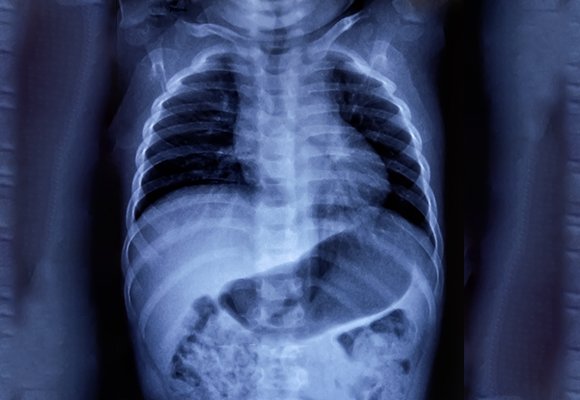

Bronchoscopy And Airway Intervention

Ruby Hall Clinic describes a daycare unit with advanced video bronchoscopy, equipped endoscopy suites, BAL, protected specimen brush biopsy, transbronchial needle aspiration, transbronchial lung biopsy, foreign-body removal, airway dilatation, electrocautery, APC, stenting, and emergency bronchoscopies in intensive care.